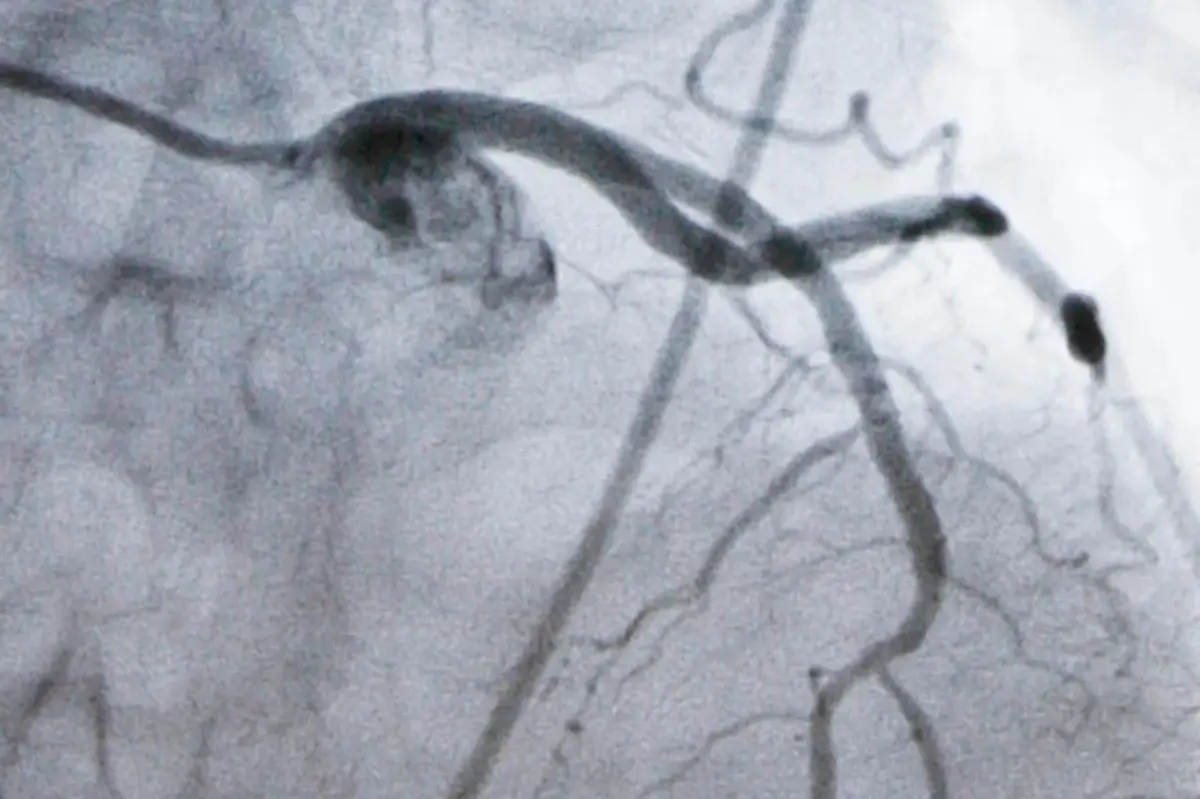

Heart disease is a leading killer in the U.S., with high LDL cholesterol being the primary risk factor for heart attacks and strokes. An LDL level of 100 is generally safe, but if you have high cholesterol or heart disease, doctors recommend reducing it to at least 70—and even lower for those at very high risk.

Statin medications, like Lipitor and Crestor, are quite effective for lowering LDL cholesterol. Additionally, some injectable drugs target a liver protein called PCSK9, which hinders the removal of cholesterol from the bloodstream. However, only a small number of patients benefit from these PCSK9 inhibitors due to costs and the complexities involved in their administration.